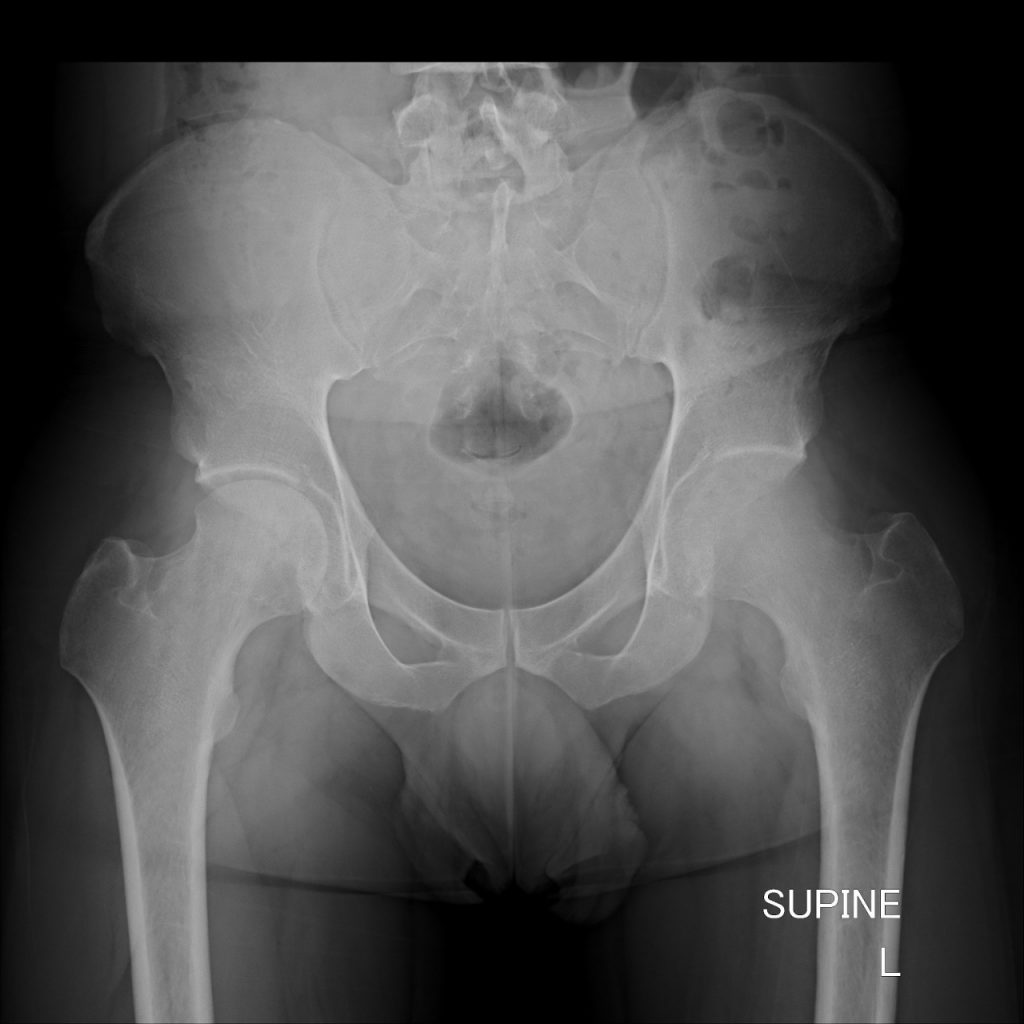

BURNT OUT RICKETS

Rickets is a disease of childhood characterized by deformities of the skeleton. It is usually the result of a vitamin D deficiency. Less commonly, it is seen as a result of a phosphate metabolic abnormality. One would not expect vitamin D deficiency in a sunny country like South Africa, but with the change of lifestyle it does become more prevalent.

These are the pre- and post-op XRs of a two-year-old with burnt out vitamin D deficient rickets.